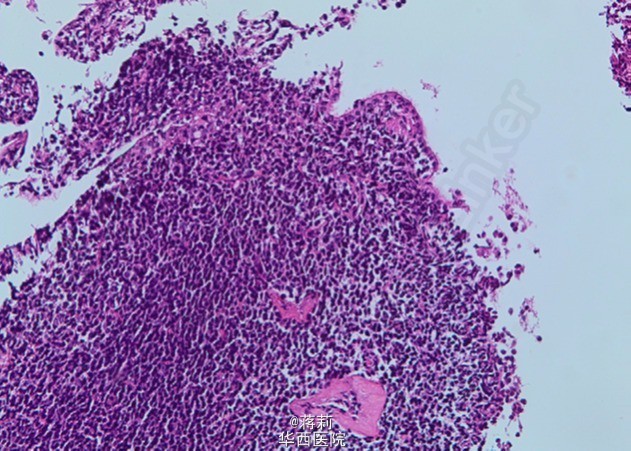

稀罕病例,大家一起来学习下!粘膜相关淋巴组织(MALT)淋巴瘤多见于胃部,而原发性肺 MALT 淋巴瘤十分罕见。来自南非开普敦 Sellenbosch 大学和 Tygerberg 医院呼吸科、血液科、病理科的数名学者近期在 Chest 杂志上报道了这样一例患者。 MALT 淋巴瘤有着较好的转归,5 年生存率达到 85% 以上,一般生存时间可超过 10 年。不像其他大多数肿瘤,即使在诊断时已有转移,也不会影响其预后或生存率。详见:http://journal.publications.chestnet.org/article.aspx?articleID=1900893